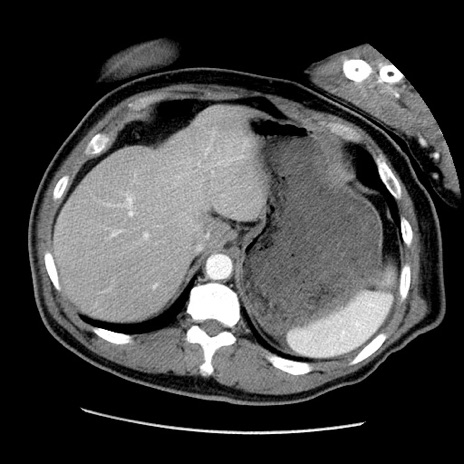

症例22(横断像)

【症例】50歳代男性

【主訴】腹痛

【現病歴】AVMからの被殻出血のため回復期リハ病棟入院中。 本日午後3時頃急に下腹部痛が出現した。

【既往歴】AVM、被殻出血、虫垂炎、高血圧

【身体所見】意識晴明、左半身不全麻痺、会話の理解は良好、36.5°C、腹部:膨隆、全体に板状硬、下腹部正中に圧痛点あり、反跳痛-、筋性防御不明、右下腹部にope scar

【データ】WBC 9400、CRP 0.06